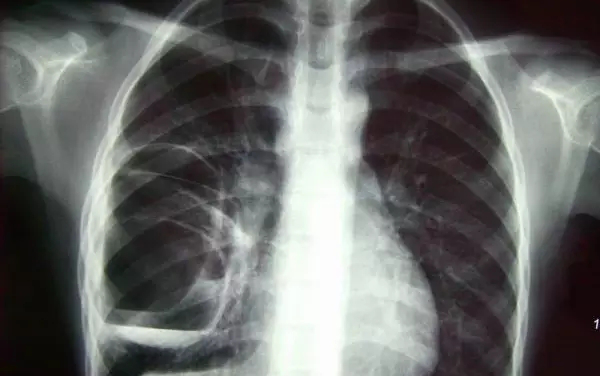

X光攝影(平片)

X光會(huì)穿透人體,由于人體各部位組織密度厚度不同,吸收的X光機(jī)的劑量不同,到達(dá)底片的X光的量不同,底片就會(huì)顯現(xiàn)出黑白不同的顏色。

優(yōu)點(diǎn):快捷、價(jià)廉、影像清晰度高

缺點(diǎn):平片檢查,無(wú)法進(jìn)行三維檢查

3、胸部——粗看X光平片,細(xì)看CT

X光胸片可粗略檢查肺、心影、主動(dòng)脈弓、肋骨等,可以檢查有無(wú)肺紋理增多、肺內(nèi)較大腫塊、主動(dòng)脈結(jié)鈣化等。胸部CT檢查顯示出的結(jié)構(gòu)更清晰,對(duì)胸部病變檢出敏感性和準(zhǔn)確性均優(yōu)于常規(guī)X光胸片,特別是對(duì)于篩查早期肺癌有重大意義。而磁共振成像對(duì)于肺內(nèi)疾病的診斷,應(yīng)用非常有限。